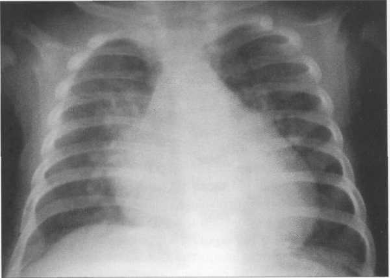

У новорожденных сердце имеет относительно большую величину, СЛК у них может достигать 58% (рис. 9.22). У более старших детей и у взрослых СЛК составляет 44—48%, для большого числа подростков характерны небольшие размеры сердца (СЛКменее 40%) (рис. 9.23),улюдей пожилого возраста поперечные размеры сердца увеличиваются, СЛК у них, как правило, более 50%.

Рис. 9.22. Рентгенограмма грудной клетки ребенка 3 месяцев. Задняя проекция.

Рис. 9.23. Рентгенограмма грудной клетки подростка. Передняя проекция.